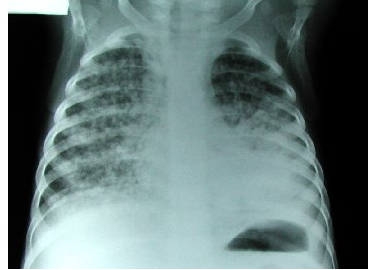

14

Q

Diego es un niño alamos

Patrón radiológico: Diseminación difusa y puntilleo en todos los pulmones “alpiste de los canarios”, “semillitas cafés”.¿Que tratamiento le vas a dar?

A

Dotbal (RIPE)

rifampicina, isoniazida piranzinamida & etambutol o estreptocina

10 W x 4 tabletas 1 dosis

TB o Hongos! Mayor riesgo de meningitis tuberculosa.

A LA MADRE SE LE PASO LA BCG